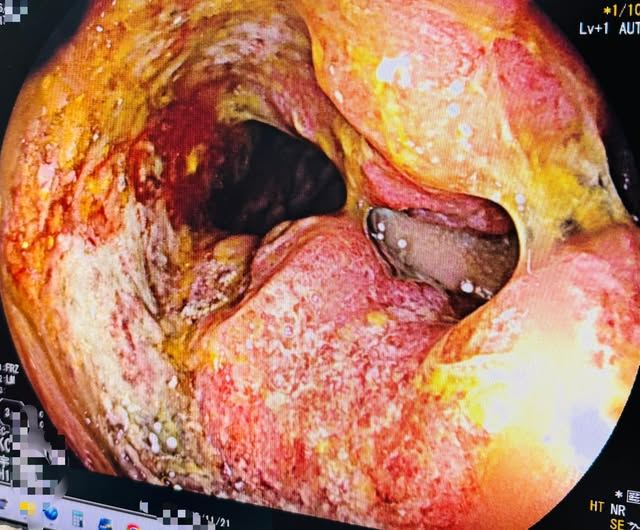

陳英傑醫師指出,最初雖然先開立藥物觀察,但回診後發現症狀毫無改善。憑藉專業直覺,他主動安排了大腸鏡檢查,不料結果顯示為直腸腫瘤,且腫瘤體積已大到引發腸道阻塞,情況不容樂觀。